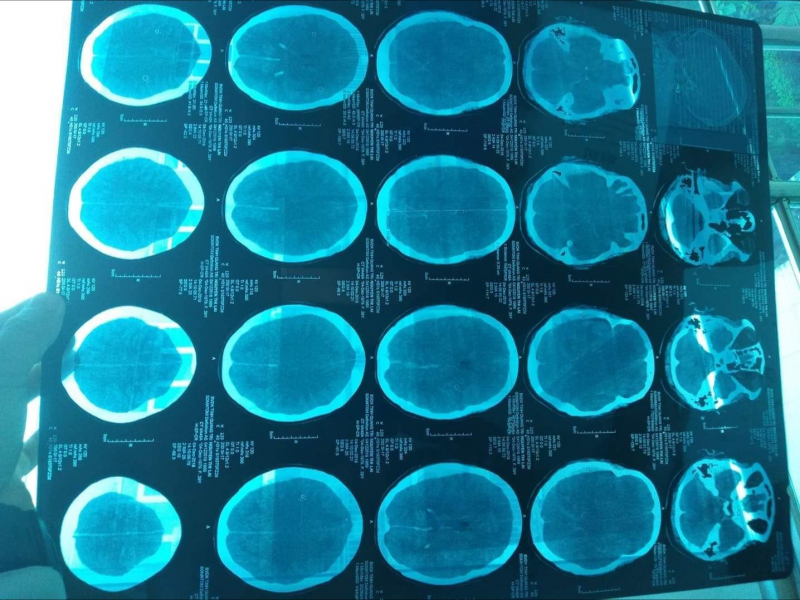

Phản ánh đến Báo Giao thông, anh Quảng cho biết: khoảng 8h30 ngày 3/12, chị Lài bị ngã xe máy nên được người nhà đưa đi cấp cứu tại Bệnh viện Đa khoa tỉnh Quảng Trị. Sau khi thăm khám, các bác sỹ nhận định chị Lài bị vết thương ở hàm mặt và tiến hành chụp CT cắt lớp. Kết quả, không phát hiện bất thường nào.

Liên quan đến vụ việc, bác sĩ Trương Xuân Nhuận, Phó Giám đốc Bệnh viện Đa khoa tỉnh Quảng Trị cho biết, các bác sĩ đã làm đúng quy trình, đúng chuyên môn và nhanh chóng. Chấn thương vùng mặt gây chấn thương sọ não kín rất nguy hiểm khiến chảy máu dưới màng cứng bán cầu não phải, xuất huyết dưới nhện và phù não 2 bán cầu.

Chị Lài được chẩn đoán ngừng tuần hoàn hô hấp do chấn thương sọ não nặng, không có chỉ đạo phẫu thuật, điều trị theo hướng hồi sức tích cực. Nếu không có sốc phản vệ thì trường hợp này tỷ lệ tử vong cũng rất cao.

“Không phải do bác sĩ dùng thuốc bậy hoặc làm không đúng chuyên môn. Đó là phản ứng dị ứng của cơ thể đối với dị nguyên hoặc thuốc, mà thuốc đó không thể không dùng được. Hôn mê này là do chấn thương sọ não nặng thể hiện bằng lâm sàng theo dõi. Mặc dù bệnh nhân tim trở lại bình thường, phổi trở lại bình thường, huyết áp lên, bệnh nhân tỉnh mà hình ảnh CT và scanner là có tổn thương não”, bác sỹ Nhuận lý giải.